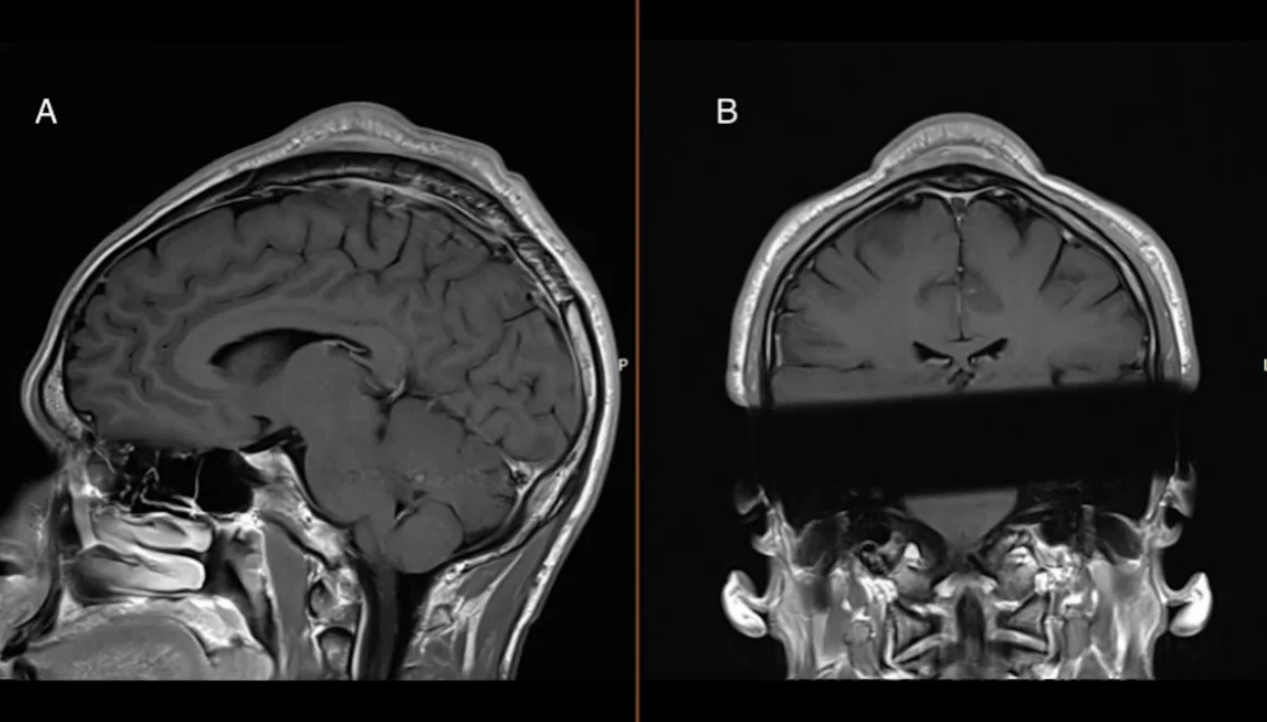

Poškodba se običajno začne z izpadanjem las, na vrhu glave pa lahko zraste velika izboklina. Danski raziskovalci so v četrtek v medicinski reviji BMJ objavili primer, ko je moški v zgodnjih 30. letih breakdance treniral skoraj 20 let. Zdravniki so ga morali zaradi omenjenega plesnega giba zdraviti zaradi benignega tumorja, ki je bil debel več kot dva centimetra.

"Menimo, da je to stanje posledica ponavljajočega se trenja med glavo in tlemi, ki se skupaj z obremenjujočo naravo headspinov nabira z leti breakdancea," je dejal dr. Christian Baastrup Søndergaard, specialist za nevrokirurgijo v bolnišnici Rigshospitalet v Köbenhavnu. "Ta ponavljajoča se obremenitev lobanje, lasišča in kože verjetno sproži vnetje, manjše krvavitve pa lahko sčasoma povzročijo zadebelitev kože in brazgotinsko tkivo, ki tvori značilno izboklino," je dejal Søndergaard, soavtor poročila o primeru, ki je bolnika zdravil.

Bolnik je pred operacijo poročal o nelagodju in bolečinah. Da bi izboklino zakril, je med ljudi hodil zgolj s pokrivalom na glavi. Ko so kirurgi izrastek odstranili, je bolnik začutil olajšanje."Super je, da grem lahko v javnost brez kape ali klobuka. Veliko ljudi mi je reklo, da izbokline ne opazijo več in da je moja glava videti povsem normalno," je dejal.